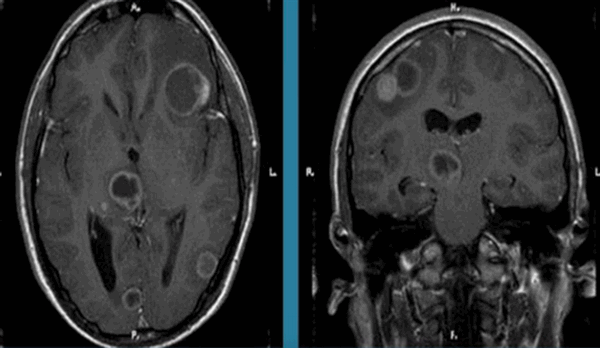

![Токсоплазмоз на МРТ головного мозга]()

Токсоплазмоз на МРТ головного мозга